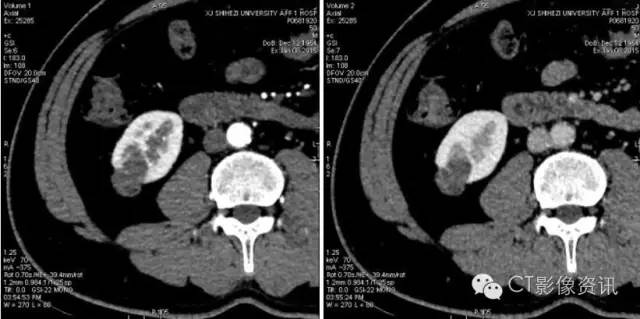

下图是横轴位5mm平扫及三期强化图像,参与病例讨论的医生半数以上认为有强化。

病灶是肯定的,讨论的焦点是有无强化,这是判断病灶性质的关键。